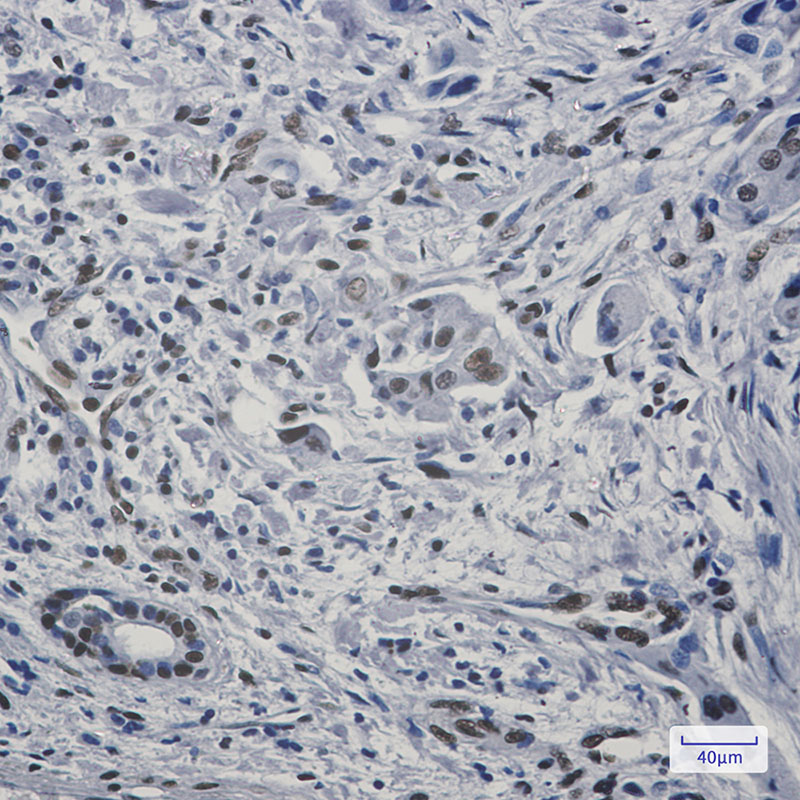

IHC 1/50-1/100 Human,Mouse,Rat

FAM98B antibodies are primarily used as research tools to investigate the protein's expression, localization, and functional roles. Immunohistochemical studies reveal its cytoplasmic localization, with enriched expression in tissues like the brain, testis, and gastrointestinal tract. Recent research links FAM98B dysregulation to pathological conditions, including colorectal cancer and breast cancer, where it may influence tumor cell proliferation and migration. Commercial FAM98B antibodies (polyclonal or monoclonal) are typically validated for applications such as Western blotting, immunofluorescence, and immunoprecipitation. However, antibody specificity remains a challenge due to potential cross-reactivity with homologous family members. Ongoing studies aim to clarify its molecular mechanisms and therapeutic potential in disease contexts.